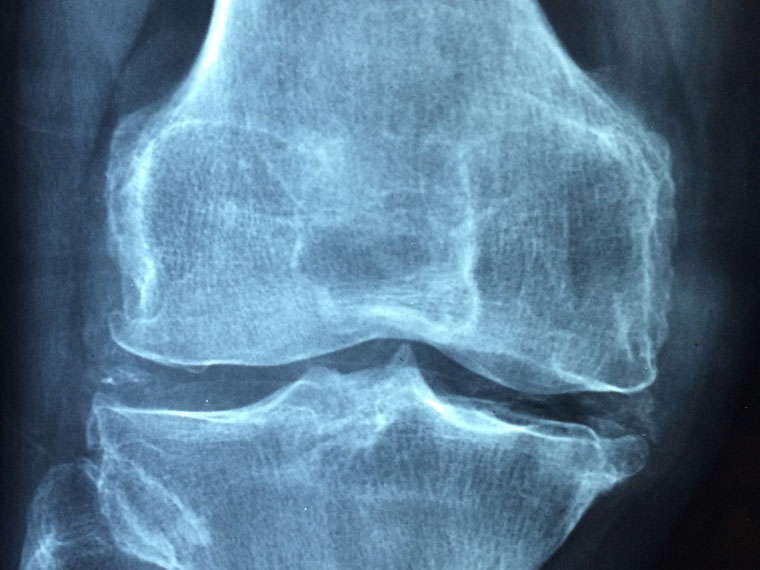

El osteólogo japonés Yoshihiro Sato se suicidó en enero de 2017, un año después de que la revista Neurology publicase un artículo que mostraba evidencias de fraude en 33 de sus trabajos, de los cuales, hasta la fecha, solo han sido retractados 21. El fraude de Sato es uno de los más recientes y escandalosos, ya que el japonés publicó más de 200 estudios sobre cómo reducir el riesgo en fracturas de hueso. Estudios que después se utilizaron como base para hacer meta-análisis y cuyas conclusiones tienen consecuencias en la práctica clínica.

La prolija actividad científica de Sato fue lo que empezó a levantar sospechas, pues en sus artículos hacía revisiones de cantidades elevadísimas de pacientes recopiladas en muy poco tiempo y en una ciudad muy pequeña. En el año 2012, un equipo de científicos que realizaban un meta-análisis con estudios que analizaban el efecto del calcio en las fracturas de cadera tomaron la decisión de omitir los datos del japonés, ya que eran demasiado buenos como para ser fiables: más bien parecían inventados.